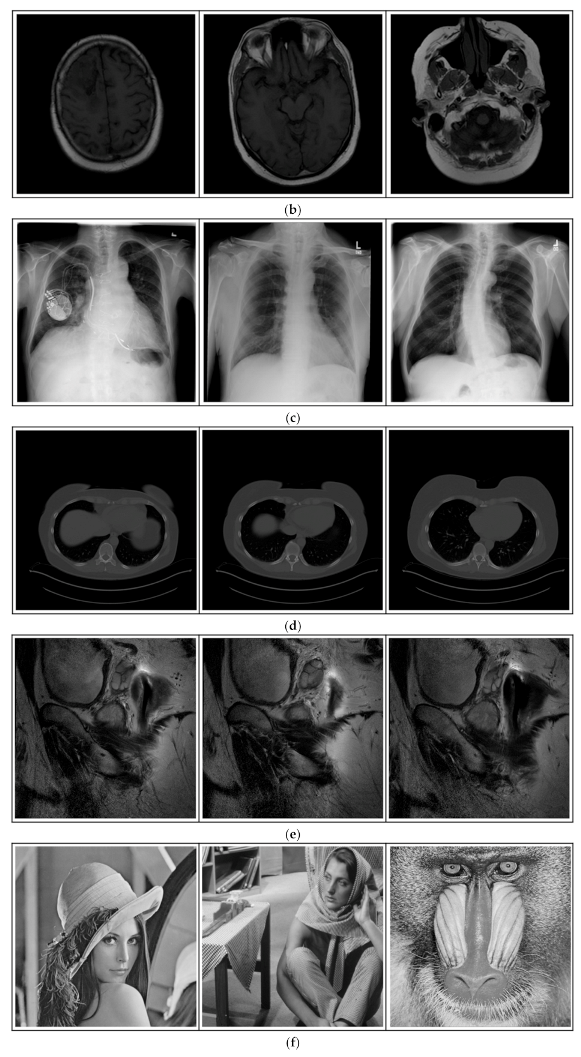

4.1. The Tested Databases

This section introduces the databases used in our experiments, including medical images and general images. As suggested by one of the anonymous reviewers, the web addresses of the involved testing databases are provided for readers’ ease of reference. The details of these databases are as follows.

(a)

Breast-MRI-NACT-Pilot Database (available at: https://wiki.cancerimagingarchive.net/display/Public/Breast-MRI-NACT-Pilot (accessed on 4 November 2021))

Breast-MRI-NACT-Pilot is an MRI-type image database, collecting breast medical images of 64 patients. Some samples are shown in Figure 12a.

(b)

ACRIN-DSC-MR-Brain database (available at: https://wiki.cancerimagingarchive.net/pages/viewpage.action?pageId=50135264 (accessed on 4 November 2021))

ACRIN-DSC-MR-Brain database contains MRI-type and CT-type brain medical images. Some samples are shown in Figure 12b.

(c)

NIH Database

ANIH is an X-ray type image database collecting chest medical images. Some samples are shown in Figure 12c.

(d)

Lung-PET-CT-Dx Database (available at: https://wiki.cancerimagingarchive.net/pages/viewpage.action?pageId=70224216 (accessed on 4 November 2021))

Lung-PET-CT-Dx is a CT-type image database collecting lung medical images. Some samples are shown in Figure 12d.

(e)

Prostate-MRI Database (available at: https://wiki.cancerimagingarchive.net/display/Public/PROSTATE-MRI (accessed on 4 November 2021))

Prostate-MRI database contains MRI-type medical images and collects prostate medical images. Some samples are shown in Figure 12e.

(f)

Other grayscale standard images

In order to investigate the flexibility of our method, we also tested several available images, as shown in Figure 12f.

Figure 12. Sampled images in the tested benchmark databases: (a) Breast-MRI-NACT-Pilot (breast), (b) ACRIN-DSC-MR-Brain (brain), (c) NIH (chest), (d) Lung-PET-CT-Dx (lung), (e) Prostate-MRI (prostate), and (f) Other grayscale standard images.

Computers 10 00152 g012aComputers 10 00152 g012b